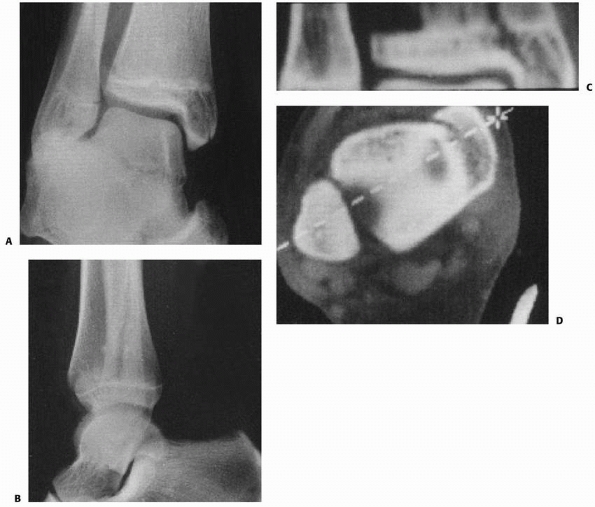

![]() |

FIGURE 26-10 A. Anteroposterior radiograph of Salter Harris type III/juvenile Tillaux Fracture. B. Lateral radiograph of Salter Harris type III/juvenile Tillaux Fracture.

|

III fracture involving the anterolateral distal tibia. The portion of

the physis not involved in the fracture is closed (Fig. 26-10).

common the appearance of a Salter-Harris type III fracture on the

anteroposterior radiographs and of a Salter-Harris type II fracture on

the lateral radiographs (Fig. 26-11). CT scans can be very helpful to understand the complex anatomy of these fractures (see Fig. 26-11). It has been proposed that the mechanism of injury for Tillaux and triplane fractures is external rotation.47,148